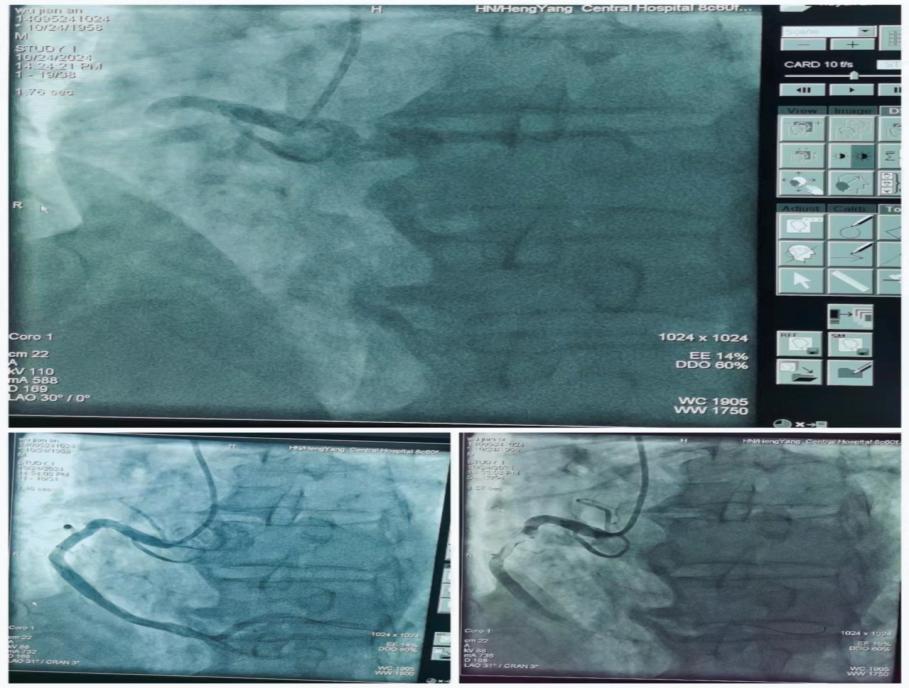

心內(nèi)科朱曉宇主任醫(yī)師急會(huì)診后,考慮Kounis綜合征-過敏性急性冠脈綜合征。與家屬溝通病情立即啟動(dòng)急性心梗急救流程,開通胸痛綠色通道送入導(dǎo)管室行急診PCI。急診冠狀動(dòng)脈造影顯示右冠第一轉(zhuǎn)折后完全閉塞并大量血栓影,賓建國(guó)副主任醫(yī)師帶領(lǐng)介入團(tuán)隊(duì)行急診右冠內(nèi)血栓抽吸+PTCA+支架植入術(shù),手術(shù)時(shí)間約40分鐘,術(shù)后病人安返心內(nèi)科病房。